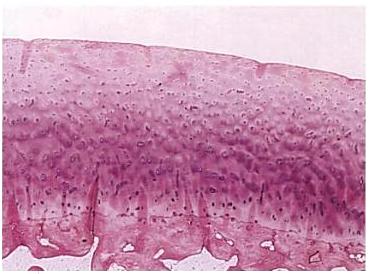

Fig. 13. Imagine microscopica a cartilajului articular sanatos.